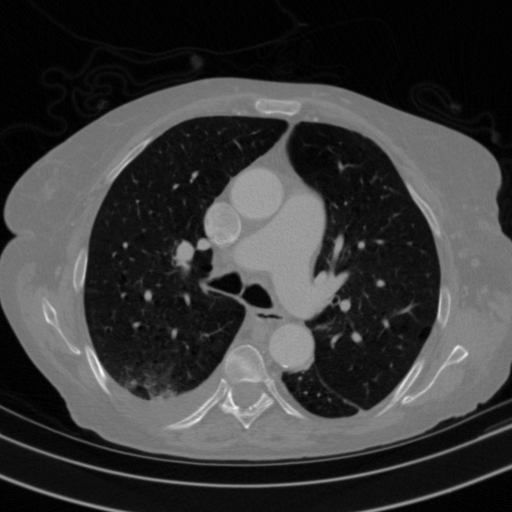

Original VENOUS CT scan

Full window (WL 1023.5, WW 4095 β†’ Low βˆ’1024, High +3071)

Actual HU range: [-1024.0, 1022.0]

Lung window (WL -600, WW 1500 β†’ Low βˆ’1350, High +150)

Actual HU range: [-1024.0, 150.0]

Mediastinum window (WL 40, WW 400 β†’ Low βˆ’160, High +240)

Actual HU range: [-160.0, 240.0]